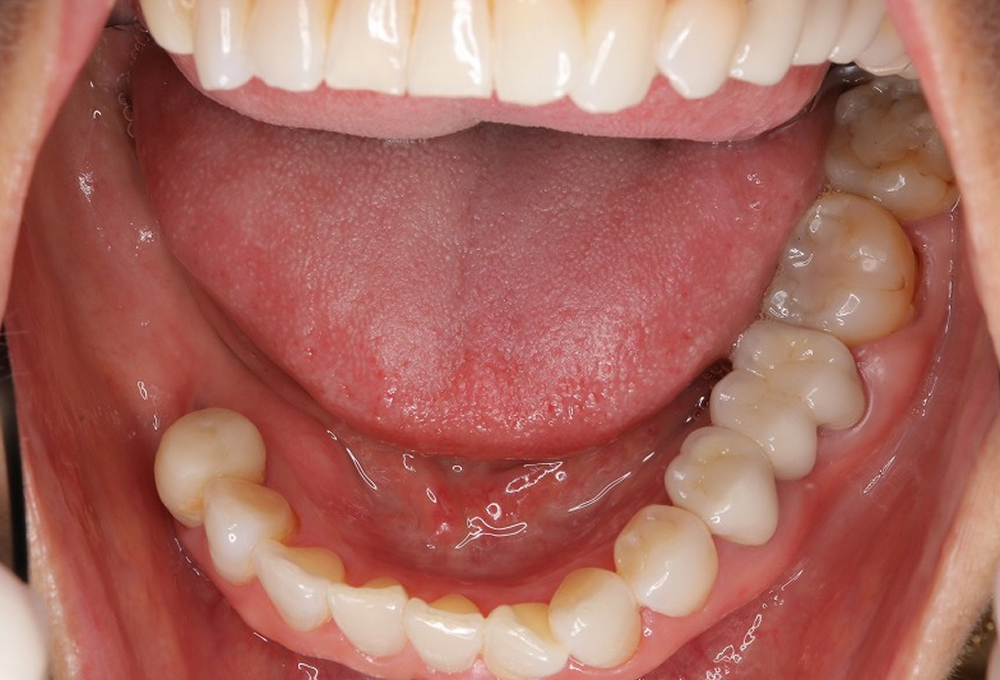

⑧術後 下顎